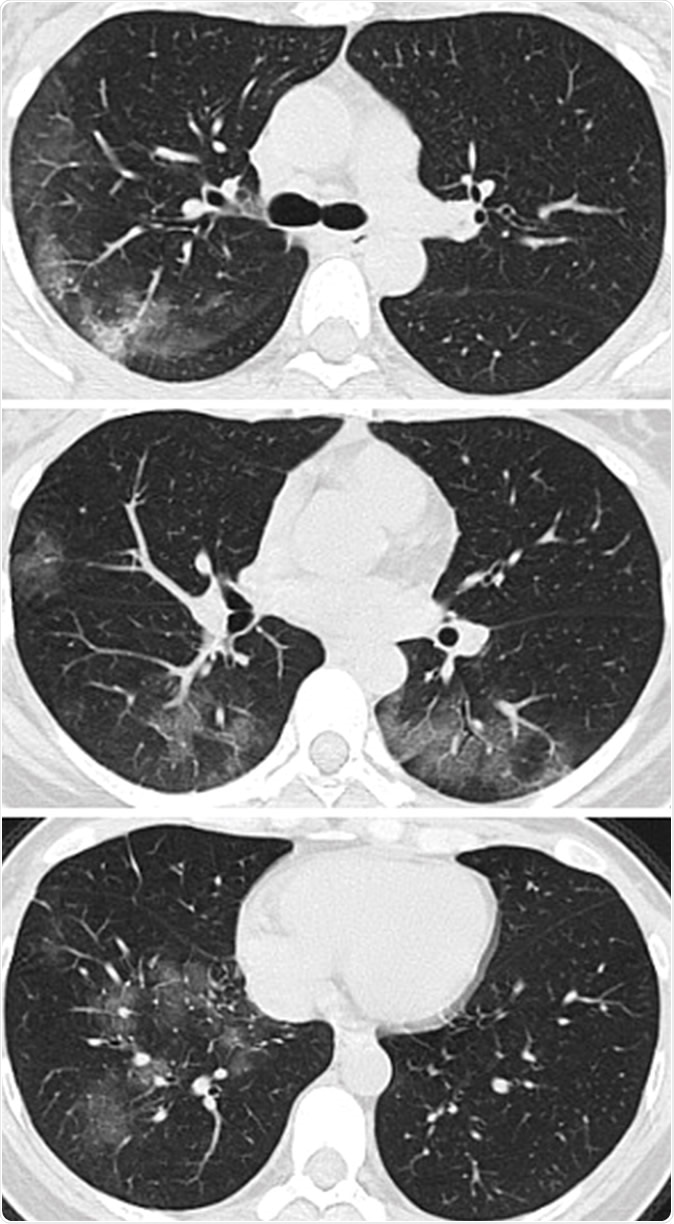

Images in a 41-year-old woman who presented with fever and positive polymerase chain reaction assay for the 2019 novel coronavirus (2019-nCoV). (a) Three representative axial thin-section chest CT images show multifocal ground glass opacities without consolidation. (b) Three-dimensional volume-rendered reconstruction shows the distribution of the ground-glass opacities (arrows). See also three-dimensional Movie (online).